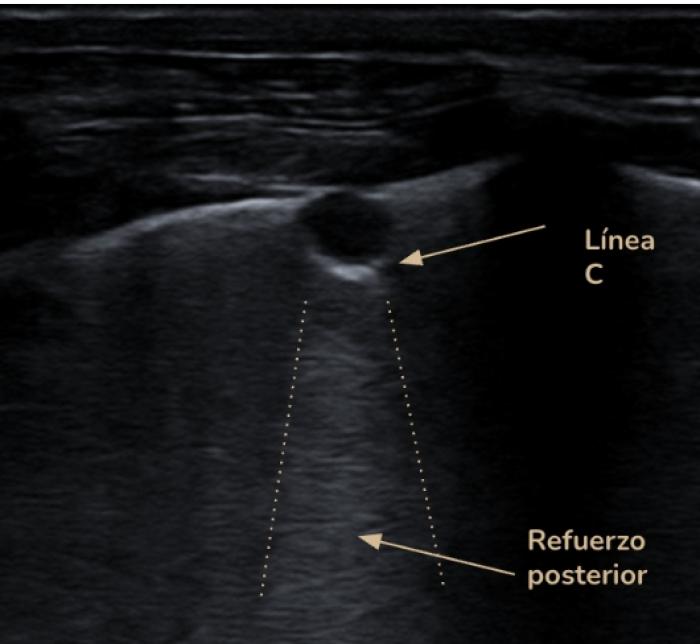

Signo nodular

Consiste en una consolidación de aspecto circular a menudo de anecoicos a hipoecoicos con rara aparición de broncogramas en su interior. Distalmente al signo nodular observamos una línea cóncava hiperecogénica llamada línea C y un refuerzo posterior o signo de brillo en la profundidad del campo. Este hallazgo es común en neoplasias primarias o metastásicas, granulomas fúngicos o abscesos. Es un signo de especial importancia cuando tenemos un paciente con historial oncológico previo o en el protocolo de búsqueda de metástasis. Los nódulos observados veremos cómo se desplazan de izquierda a derecha de la imagen con la respiración del paciente, haciendo patente que se encuentran a nivel pulmonar y no de la pared costal, en cuyo caso no se desplazaran mientras el transductor se encuentre inmóvil (Figura 16A-D).